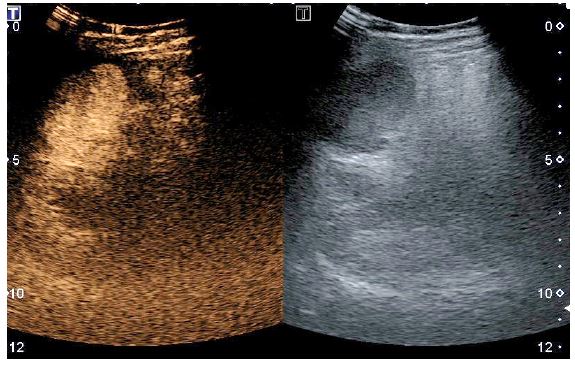

The surgical specimen (Figure 6) was extracted with an endobag through the 15 mm incision and a drainage was placed in the splenic bed. The postoperative period was uneventful. A CEUS was performed five days after surgery showing that the residual spleen maintained a normal perfusion of the parenchyma [7]. At 12-month follow up, CEUS confirmed the absence of recurrent splenic cysts and the normal perfusion of the remnant spleen (Figure 7).

Figure 7: Contrast enhanced ultrasonography 12 months after surgery.